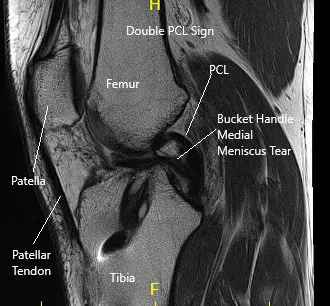

La resonancia magnética de la rodilla derecha sugirió una gran ruptura en forma de mango de cubo del menisco medial, desplazada hacia la muesca intercondilar y sobre el cuerno anterior.

Resonancia magnética de la rodilla derecha en la sección sagital y coronal.